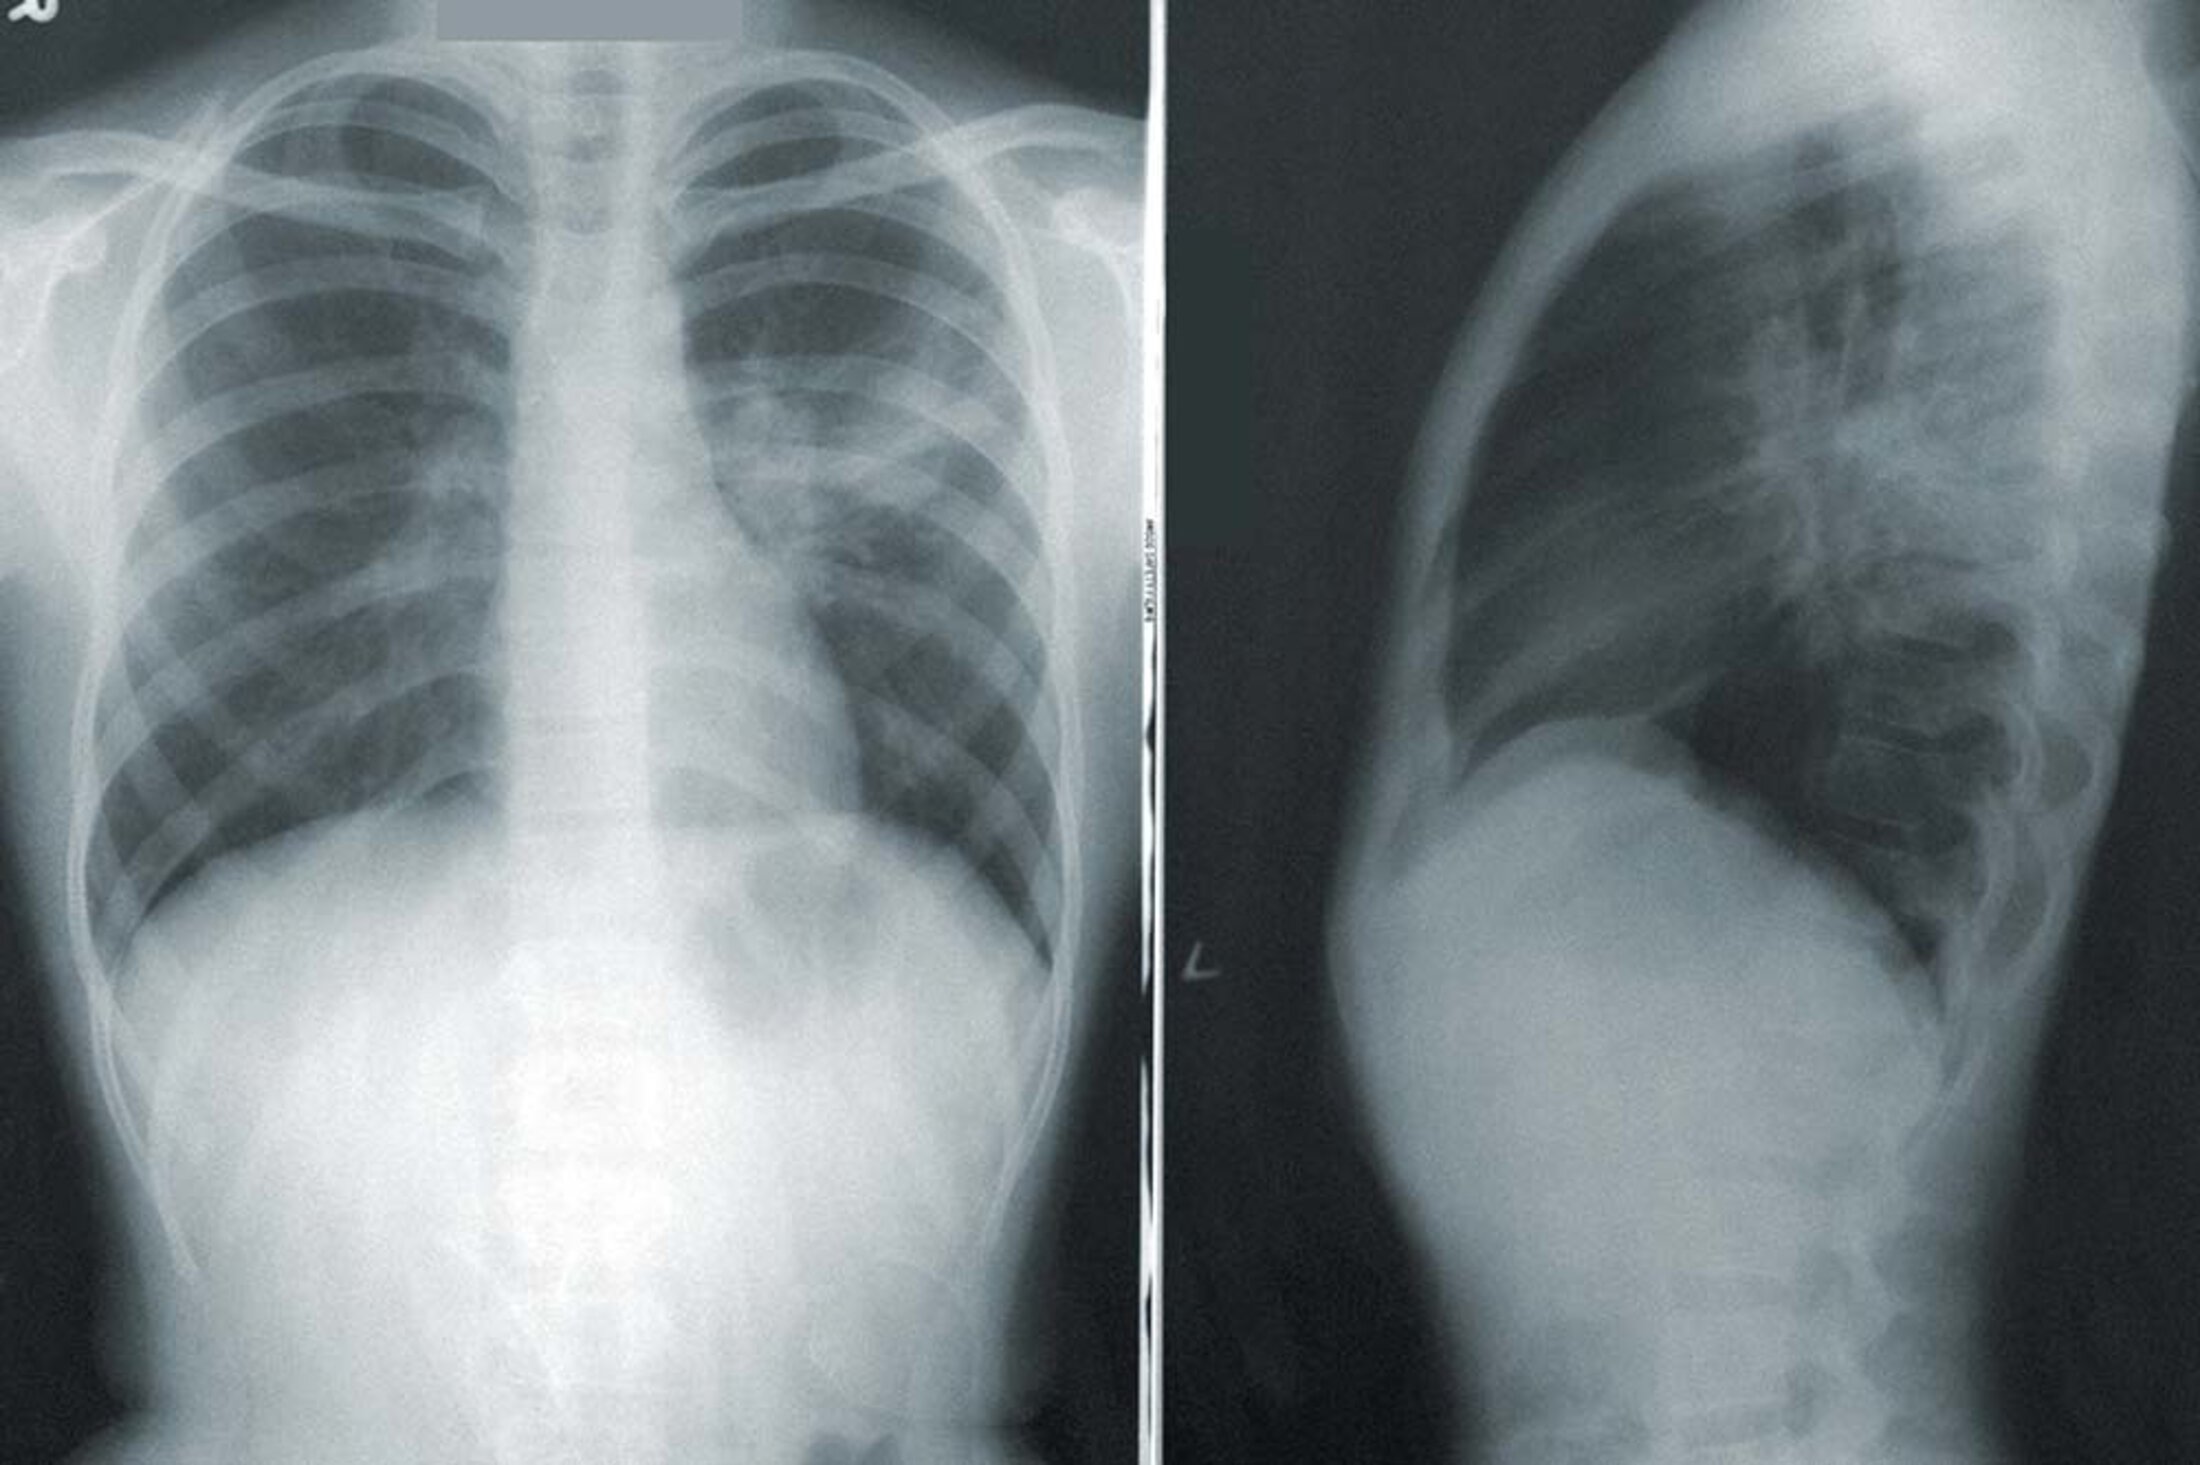

The cloudy area shows where fluid has accumulated in the lungs of a person with pneumonia. Image by Centers for Disease Control and Prevention

From there, unwanted fluid builds up in the lungs. “Whenever we're exposed to something, whether it's virus or bacteria, our immune system tries to identify it and then clear it out with our own defenses. And part of that defense creates inflammation. Some of the debris from that inflammation, which is hopefully killing some of the bacterial cells, can lead to pus in the lungs.”